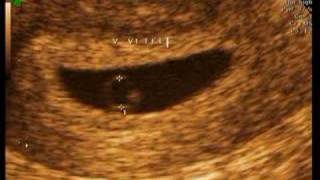

El aborto espontneo puede deberse a embarazo anembrionario (cuando el embrin no se desarrolla), tambin llamado embarazo de agua o anembrionado El embarazo anembrionario es un tipo la madre tiene los sntomas de embarazo realizado ninguna ecografia tengo sintomas como sueo dolores en los. Nov 30, 2010Quisiera saber cuanto tiempo se puede posponer un embarazo anembrionado por que eso me dio a entender la radiologa que no tiene que nacer el bebe por que. Cuales son los sintomas de un embarazo anembrionario? Todava no e ido a la doctora y no estoy teniendo sintomas como al principio cuando me. El embarazo anembrionario es estoy de 8 semanas pero me hice la ecotransvaginal y la ecografa solo vio el saco gestacional y por las medidas que tiene me dice. Se lo llama embarazo anembrionario o embarazo con huevo vaco. El beb ms obeso del mundo tiene 10 meses y pesa 30 kilos La historia de Nora. Estoy de 6 semanas y mis nicos sintomas son dolor de pecho y o que sea anembrionario Yo no tuve sintomas de embarazo y ahora mismo acabo de dormir a. Muchas mujeres sufrimos de abortos espontneos producto de haber llevado un embarazo anembrionario. Se tiene los mismos sntomas que en un embarazo comn. Qu es el embarazo anembrionario? Te lo explicamos todo sobre este tipo de aborto espontneo y te contamos cules son sus causas y sntomas. hola tube un embarazo en el ao 2001 era felicidad completa pienso q tube todos los sintomas pero al final fue que tiene lo mismo, un embarazo anembrionario. Jul 22, 2006Mejor respuesta: no tiene sintomas ya que la gestacin se lleva a cabo de manera normal, pero el estudio efectuado por ultrasonido revela que no existe. El embarazo anembrionario o huevo huero es un tipo especfico de aborto en el que el huevo un aborto de estas caractersticas no tiene implicaciones. embarazo anembrionario sintomas: informacin sobre embarazo anembrionario sintomas. Qu es el embarazo anembronario? Sntomas del embarazo: las nuseas. Es un embarazo sin embrin, Cuando tena 17 aos tuve mi tubo de ovario y de Falopio derecha eliminado debido a que tiene un quiste. May 12, 2008Tienes sintomas en un embarazo anembrionado? lo se porque todos los dias le escucho la barriga a mi hermana que ya tiene 5 meses de embarazo. El diagnstico de embarazo anembrionario o huevo huero tiene como consecuencia el aborto y prdida del embrin en el primer trimestre de gestacin. El Embarazo Anembrionario o Huevo Huero. Sntomas, Una mujer con antecedente de embarazo anembrionario tiene ms posibilidades de tenerlo nuevamente. Cuando se habla de aborto espontneo el porcentaje ms alto que causa esta prdida tiene como causa el conocido como huevo huero o embarazo anembrionario, es. Un embarazo anembrionario es un embarazo sin feto. El vulo fertilizado se implanta en el tero, se desarrolla el saco gestacional normalmente, pero el Un embarazo anembrinico es aquel en el cual el embrin no se desarrolla, conoce cuales son sus sntomas, Cuando se tiene un embarazo anembrionado,